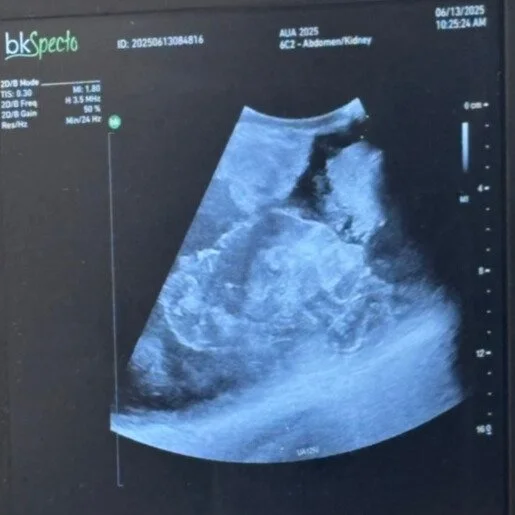

The KPP is an ideal training model for training in renal ultrasound. The phantom has been validated using multiple transabdominal ultrasound probes which demonstrate clear imaging of all the pathological components. Multiple procedures can be performed on this phantom including renal and tumor biopsy, renal collecting system access (by US-guided puncture), complete percutaneous lithotripsy including stone break up, ureteroscopy and lithotripsy, resection of mucosal based tumors and percutaneous kidney tumor ablation (cryotherapy, RFA). The phantom is fully customizable including kidney tumor, stone and mucosal lesion size and location. The phantom can be ordered with a CT or MRI file.